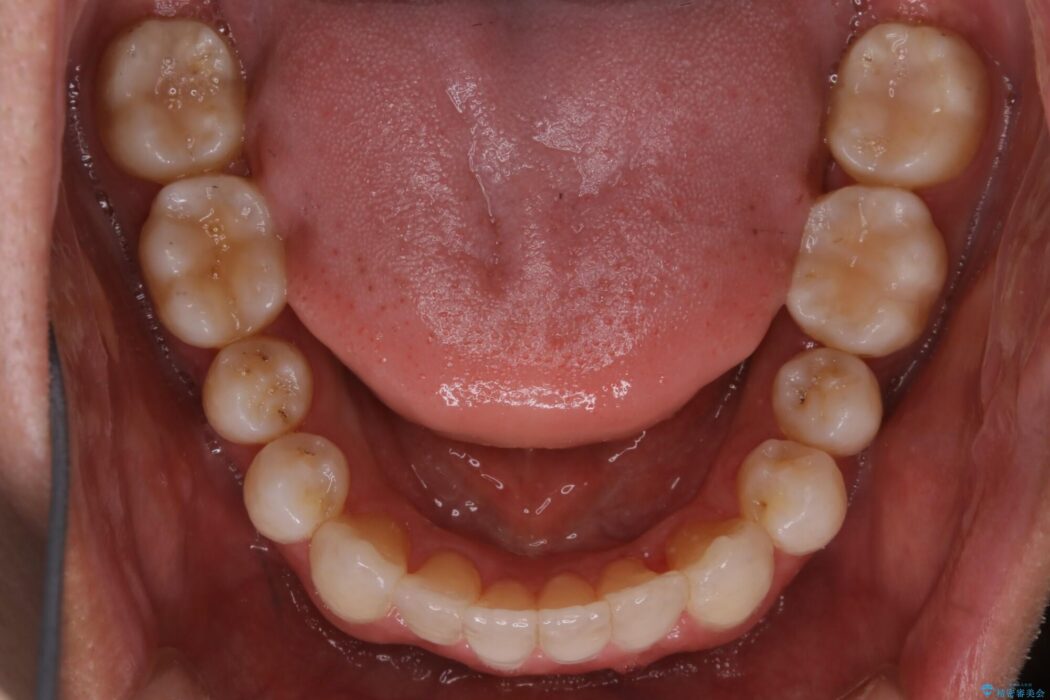

上顎歯列弓のガタガタを治療したいとのことで来院されました。

前に出ていた前歯や目立つ八重歯(3番目の歯)もきれいに並び、奥歯の虫歯治療も並行して行ったため、機能面でも見た目的にも良くなり満足していただきました。